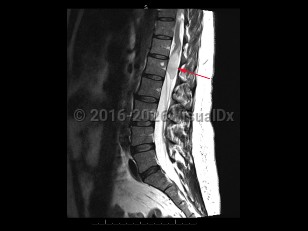

Cauda equina syndrome is a neurologic emergency where damage to the lumbosacral plexus leads to loss of lower motor neuron function. Trauma, tumors or abscesses, large lumbar disk herniation, and spinal stenosis are some of the etiologies of this condition.

Onset is typically gradual but can be acute. Signs and symptoms include severe back pain that may radiate into one or both legs, saddle anesthesia, leg weakness or paraplegia, urinary or bowel dysfunction, sexual dysfunction, and gait disturbance. There may be reduced or absent patellar, Achilles, anal, and bulbocavernosus reflexes.

Prognosis depends on severity and duration of compression or damage to the affected nerves.